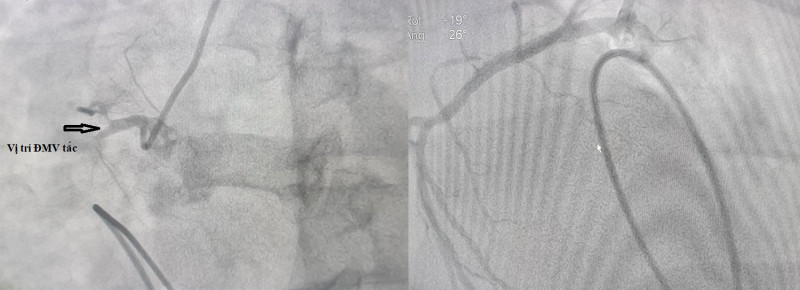

Ngay lập tức, các bác sĩ đã xử trí nâng huyết áp, chuyển thẳng bệnh nhân đến phòng can thiệp tim mạch đặt máy tạo nhịp tim tạm thời với điện cực trong buồng tim. Kết quả chụp mạch vành trên hệ thống chụp mạch số hóa xóa nền DSA phát hiện động mạch vành phải tắc hoàn cuối đoạn 1.

Nhóm bác sĩ can thiệp nong bóng, đặt 1 stent vào động mạch vành phải để tái thông dòng chảy cho mạch vành tưới máu cơ tim cải thiện. Ngay sau can thiệp, cơ tim hồi phục hoàn toàn, nhịp tim quay về nhịp xoang đều 80 lần/phút, bệnh nhân thoát nguy kịch.